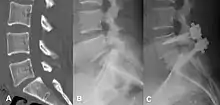

Anterolisthesis L5/S1

Anterolisthesis L5/S1. Blue arrow normal pars interarticularis. Red arrow is a break in pars interarticularis